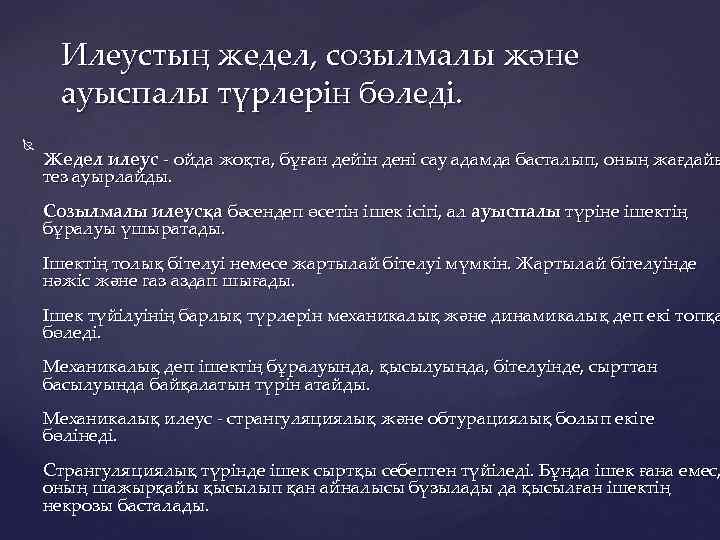

Илеустың жедел, созылмалы және ауыспалы түрлерін бөледі. Жедел илеус - ойда жоқта, бұған дейін дені сау адамда басталып, оның жағдайы тез ауырлайды. Созылмалы илеусқа бәсендеп өсетін ішек ісігі, ал ауыспалы түріне ішектің бұралуы үшыратады. Ішектің толық бітелуі немесе жартылай бітелуі мүмкін. Жартылай бітелуінде нәжіс және газ аздап шығады. Ішек түйілуінің барлық түрлерін механикалық және динамикалық деп екі топқа бөледі. Механикалық деп ішектің бұралуында, қысылуында, бітелуінде, сырттан басылуында байқалатын түрін атайды. Механикалық илеус - странгуляциялық және обтурациялық болып екіге бөлінеді. Странгуляциялық түрінде ішек сыртқы себептен түйіледі. Бұңда ішек ғана емес, оның шажырқайы қысылып қан айналысы бүзылады да қысылған ішектің некрозы басталады.

Странгуляцияға ішек бұралуы, байлануы, қысылуы, күрмелуі себеп болады. Обтурациялық түрінде ішек ісікпен, аскаридамен, дәкелі құрғатқыш (операцияда ұмытылған) бітеледі. Қан айналысы онша бұзылмайды. Өйткені шажырқай қысылмайды. Ішек түйілуінің келесі себебі инвагинация - ішекке ішек еніп оның бітелуіне қоса шажырқайдың қысылып, қан айналысы бұзылуы байқалатындығынан илеустің бұл түрінде обтурация және странгуляция қоса байқалады. Ішектің қабырғасының тегіс етінің әлсізденуіне байланысты кездесетін ішек түйілуі динамикалық деп аталады. Илеустің бұл түрін тырысқан және салды деп екіге бөледі. Спастикалық түрі - ішек қабырғасының тырысуынан оның өзегі тарылуымен байланысты болса, паралитикалық илеусте ішек созылған, өзегі кеңіген, оның тонусы - қозғалуы нашарланған.